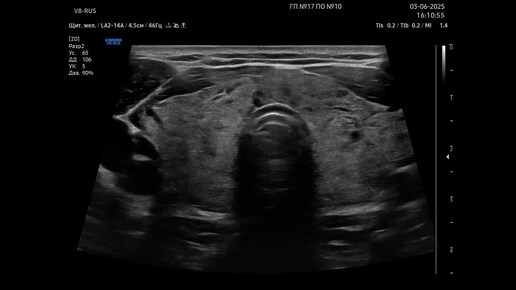

Ультразвуковая диагностика (УЗИ). Доктор Иогансен. Видеопримеры. Выпуск 127. Диффузный зоб.